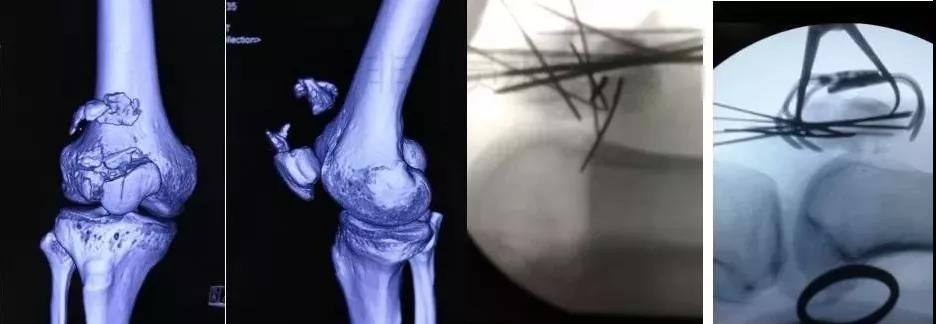

7)胫骨远端(pilon,踝部)

- pilon骨折,高能损伤,6-8h肿胀未形成,可以急诊做,手术时间<3小时。

- 10-14天,分步延期手术策略。

- 踝部骨折手术时机同样取决于皮肤条件。